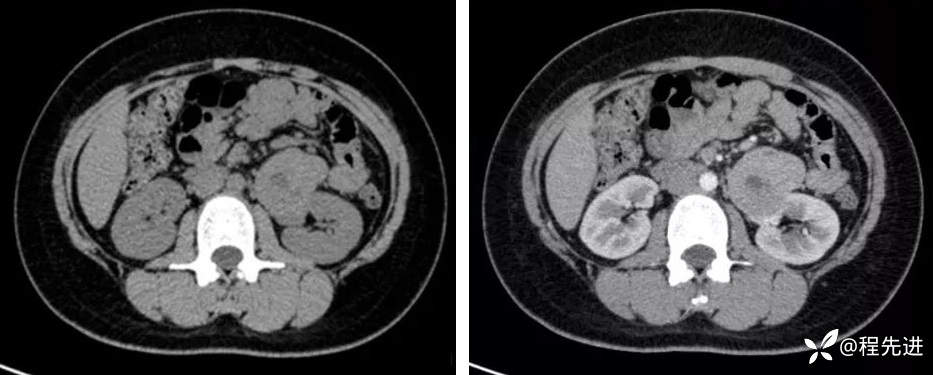

CT平扫+增强:

平扫,皮质期: